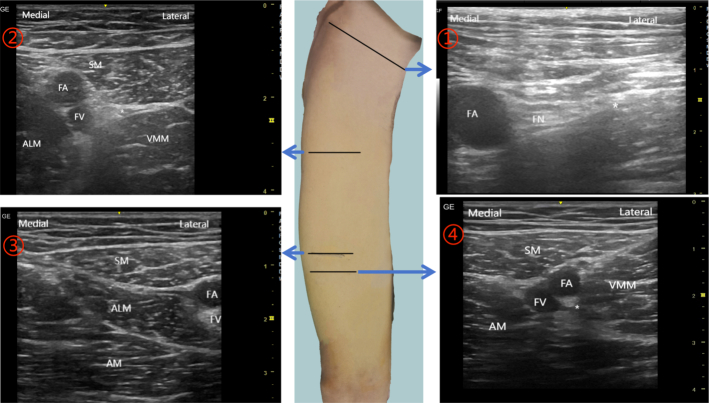

Objectives: This study aimed to compare the analgesic effects of continuous femoral nerve block (FNB), femoral triangle block (FTB), and adductor canal block (ACB) following total knee arthroplasty (TKA). The goal was to identify the most effective nerve block technique among these.

Methods: Patients undergoing TKA were randomly assigned to 1 of 3 groups: FNB, FTB, or ACB. Nerve blocks were administered preoperatively, with catheters placed for patient-controlled nerve analgesia (PCNA). The primary end point was the Numeric Rating Scale (NRS) score at movement at 24 hours postsurgery. Secondary end points included NRS scores at rest and movement, quadriceps strength, Timed Up and Go (TUG) test performance, range of motion, effective PCNA utilization, and opioid consumption at various postsurgery time points.